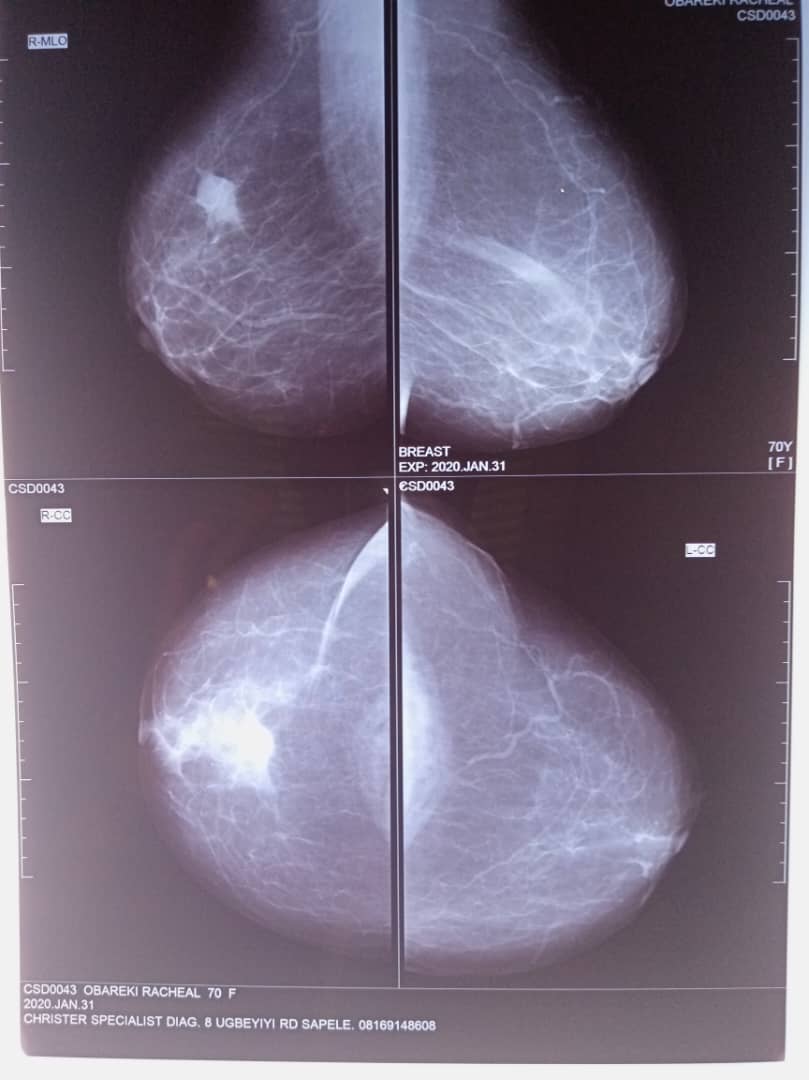

- Mammography

Mammography utilizes low dose x-rays to generate images of the breasts in search for abnormalities especially cancer at its early stage. Although mostly done for women, to screen for and diagnose breast cancer, it is also done occasionally for men with suspicious breast swellings to exclude possible breast cancer.